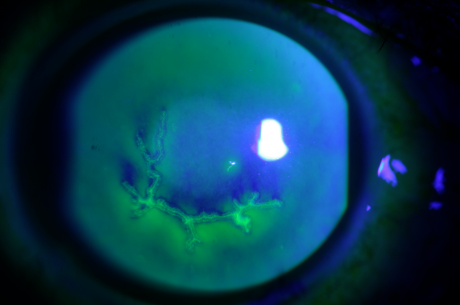

4. Drug toxic corneal epithelial lesions often occur on the basis of primary corneal diseases, which are mostly caused by the toxic accumulation of drugs and preservatives. The typical manifestation is pseudodendritic exfoliation of epithelium, accompanied by a long-term history of eye drops.

Figure 5. Drug induced corneal epithelial damage, presenting pseudodendritic epithelial defects